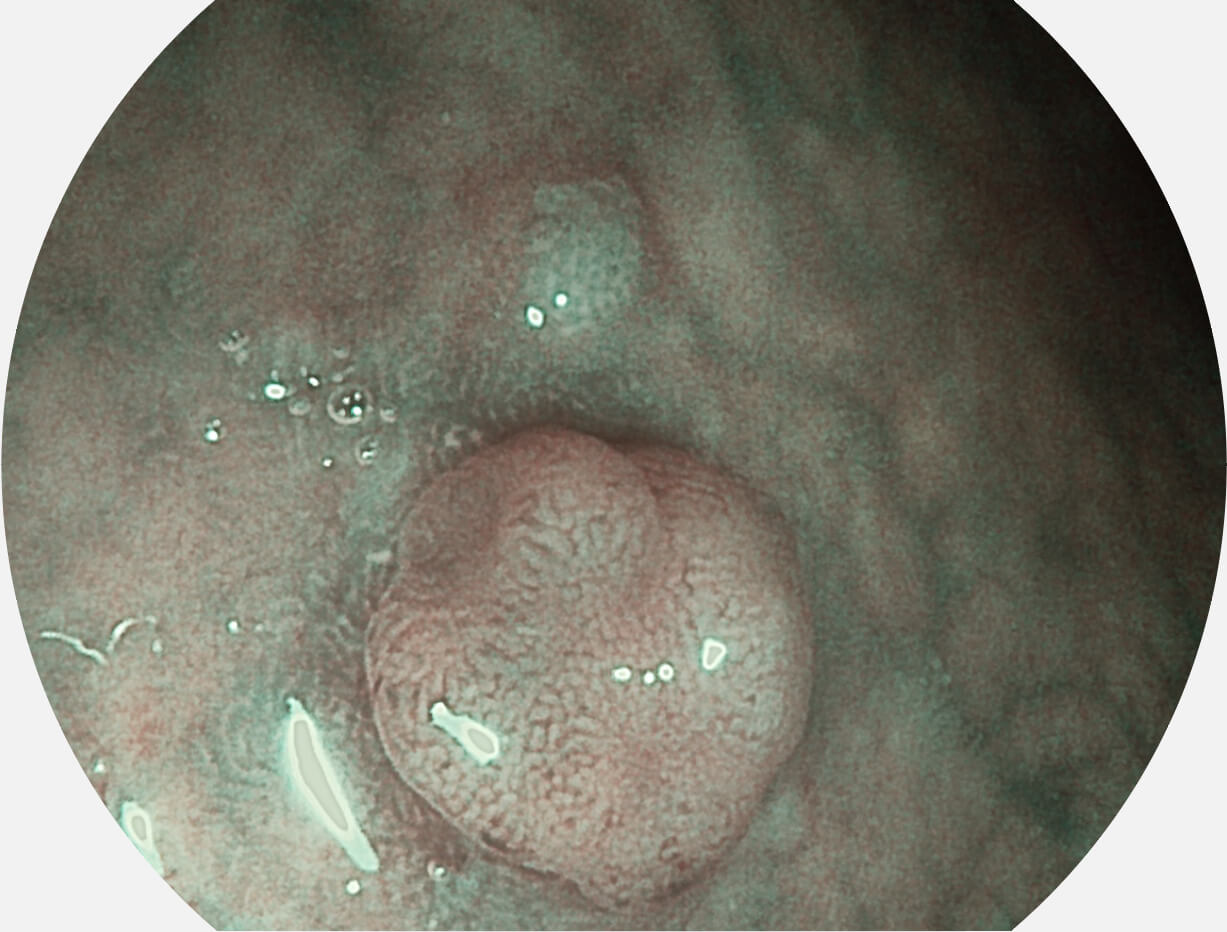

图像具有高亮度、高黏膜血管颜色对比度的特点,且不改变粘液、食物残渣、粪便的基本颜色,可在中远景下进行观察,助力消化道早期疾病的诊断。

白光图像

SFI图像